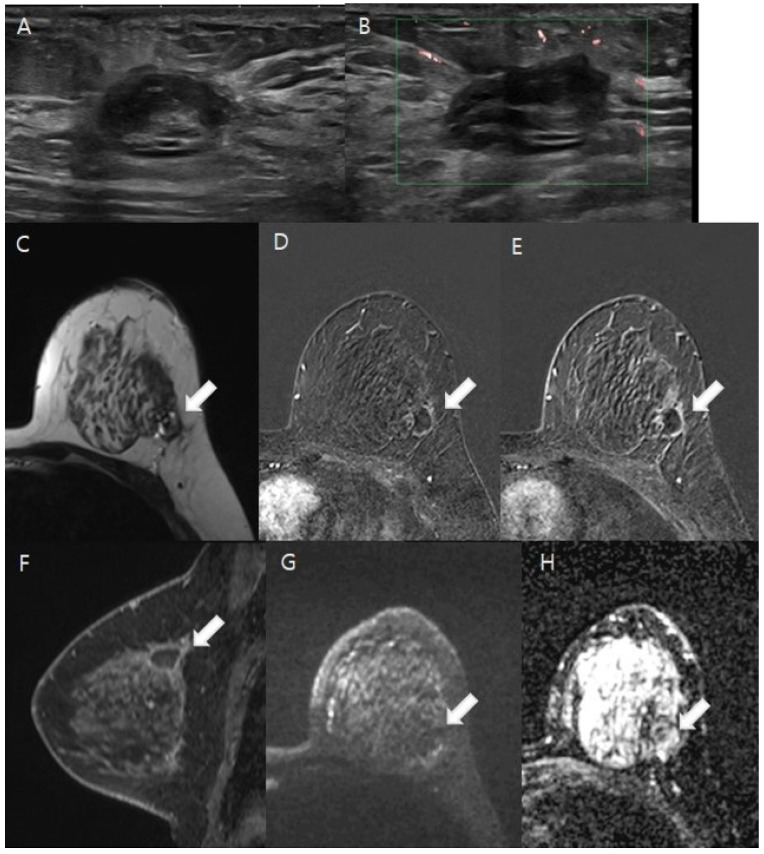

Objectives: To evaluate the effectiveness of breast MRI, including diffusion-weighted imaging (DWI), in detecting residual lesions in patients with malignancy after excisional biopsy.

Methods: From January 2018 to December 2023, 3T breast MRI was performed to assess lesion morphology, residual size, and enhancement kinetics. The apparent diffusion coefficient (ADC) values were measured, and the diagnostic outcomes of CE-MRI, CE-MRI with DWI, mammography (MG), and ultrasound (US) were compared with clinical and histopathological data.

Results: A total of 152 lesions were analyzed, with 36.2% showing residual malignancy. Both CE-MRI and CE-MRI with DWI effectively identified residual lesions, with significant differences in morphology, size, kinetic patterns, and ADC values (all p < 0.001). CE-MRI with DWI showed a sensitivity of 90.9% and an NPV of 93.6%, compared with 89.1% sensitivity and 92.2% NPV for CE-MRI alone. Sensitivities for MG and US were 57.1% and 38.7%, with NPVs of 64.7% and 59.6%, respectively. Diagnostic accuracy was highest for CE-MRI with DWI (80.9%), followed by CE-MRI (79.0%), MG (60.3%), and US (59.7%). The AUC for CE-MRI with DWI (0.831) was slightly higher than CE-MRI alone (0.811), though not significant (p = 0.095). AUCs for MG and US were lower at 0.623 and 0.563, with no significant difference between MG and US (p = 0.234).

Conclusions: CE-MRI with DWI and CE-MRI alone were comparable and demonstrated excellent performance in discriminating between women with and without residual disease. Integrating CE-MRI with DWI could become a standard protocol for patients with suspected residual malignancy after excisional biopsy.